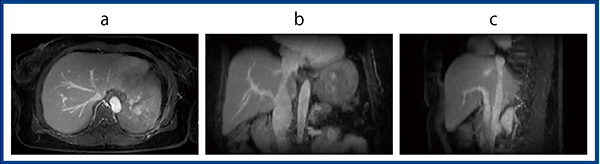

t-Multi CNNでは,少ない枚数で時間分解能を向上させた“high-speed stack-of-stars acqusition”で得られた画像をトレーニングデータセットとしている。少ないスポーク数で再構成されるstack-of-stars画像では,ストリークアーチファクト低減のためview sharingを用いるが,時間分解能が低下し再構成画像がぼやけてしまう弊害がある。今回新たに提案したt-Multi CNNでは,時間分解能を向上させたデータセットを用いることで,時間分解能とview sharingによる空間解像度の向上を両立できる(図4)。図5は,t-Multi CNNを用いたdynamic撮像のMPR画像だが,撮像枚数50枚,スライス厚4mm程度,自由呼吸下で時間分解能の高い画像が得られている。

stack-of-starsで収集したデータをt-Multi CNNで再構成した画像と,4.5秒/1フレームの時間分解能でview sharingなし(No-VS),view sharingが5倍のlevel5を使った画像(VS5)を作成し,定量・定性評価を行った(図6)。

図5 t-Multi CNNによるdynamic MRI:3方向断面

a:axial b:coronal c:sagittal